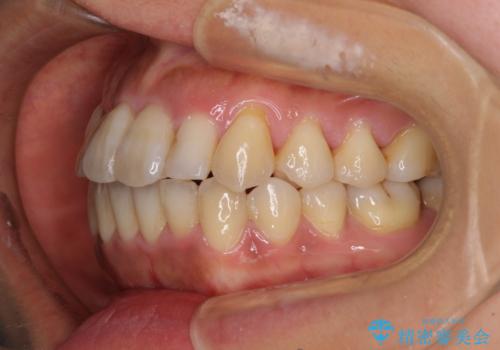

狭い上顎骨を拡大 著しい叢生を抜歯矯正で改善

治療途中、長期間海外旅行をされたり、帰国後には遠方へ転居されたりと、治療期間が伸びましたが、2年強で治療を終えることができました。